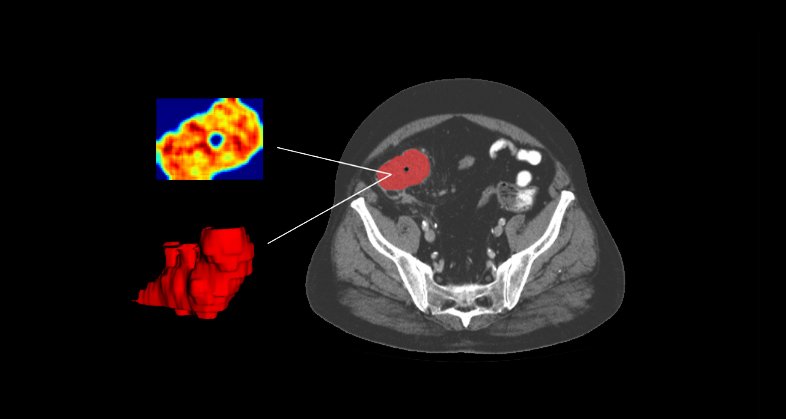

The standard therapy for diffuse large B-cell lymphoma (DLBCL) – R-CHOP – is ineffective in about one-third of patients. Early identification of these patients is crucial for testing alternate treatments. In a retrospective study, we explored the predictive value of 18F-FDG PET/CT imaging (radiomic and conventional PET parameters), clinical data, and genomic parameters, either alone or combined, for a complete response to first-line treatment in newly diagnosed DLBCL.

All the visible lesions at pre-treatment were segmented in entirety to assess tumor burden and imaging features were extracted from them. Predictive models for treatment response were developed using multivariate logistic regression, either with clinical and imaging features or with these features plus genomic features. Manual selection or linear discriminant analysis (LDA) for dimensionality reduction was used for imaging feature selection. Performance was gauged using confusion matrices and specific metrics. Thirty-three patients were included (median age 58 years, range 49-69); 23 of them (70%) achieved a complete long-term response.

Whole body 18F-FDG PET/CT imaging exam of a patient with DLBCL in the coronal plane (left) and segmentation mask where every lesion is a unique label (right)

The combination of 18F-FDG PET/CT-derived imaging features (GLSZM_GrayLevelVariance, Sphericity, and GLCM_Correlation), clinical variables, and genomic data successfully predicted complete response to first-line treatment in DLBCL patients, with BCL6 amplification being the most predictive genetic marker. The combined model (radiomic plus clinical data) built using LDA and including genomic data showed an AUC of 0.904, 90% balanced accuracy vs AUC of 0.891, 80.7% balanced accuracy for the model that combined clinical data plus radiomic features.